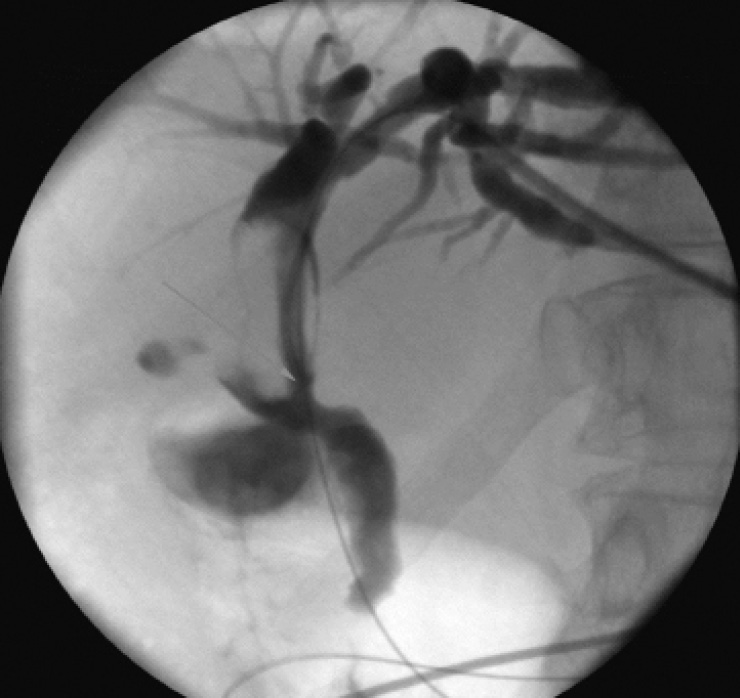

В октябре 2019 г. у пациентки появилась жалобы на желтушность кожного покрова и слизистых, общую слабость, умеренную, ноющую боль в эпигастральной и правой подреберной областях, повышение температуры тела до фебрильных цифр. Больная была госпитализирована с диагнозом «механическая желтуха, холангит». Попытки эндоскопического редренирования желчных протоков оказались безуспешны. При выполнении чрескожной чреспеченочной холангиографии в месте слияния культи правого долевого и левого долевого протоков с переходом на гепатикохоледох определялась злокачественная стриктура (Bismuth II). Контрастный препарат в гепатикохоледох, двенадцатиперстную кишку не поступал. Выполнено чрескожное чреспеченочное наружновнутреннее дренирование желчных протоков единственной левой доли печени. Установлен желчный дренаж диаметром 8,5 F (рис. 1).

Рис. 1. Чрескожное чреспеченочное наружновнутреннее дренирование желчных протоков единственной левой доли печени